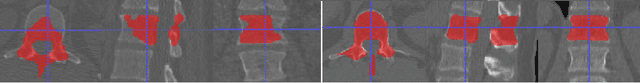

Abstract:The vertebral levels of the spine provide a useful coordinate system when making measurements of plaque, muscle, fat, and bone mineral density. Correctly classifying vertebral levels with high accuracy is challenging due to the similar appearance of each vertebra, the curvature of the spine, and the possibility of anomalies such as fractured vertebrae, implants, lumbarization of the sacrum, and sacralization of L5. The goal of this work is to develop a system that can accurately and robustly identify the L1 level in large heterogeneous datasets. The first approach we study is using a 3D U-Net to segment the L1 vertebra directly using the entire scan volume to provide context. We also tested models for two class segmentation of L1 and T12 and a three class segmentation of L1, T12 and the rib attached to T12. By increasing the number of training examples to 249 scans using pseudo-segmentations from an in-house segmentation tool we were able to achieve 98% accuracy with respect to identifying the L1 vertebra, with an average error of 4.5 mm in the craniocaudal level. We next developed an algorithm which performs iterative instance segmentation and classification of the entire spine with a 3D U-Net. We found the instance based approach was able to yield better segmentations of nearly the entire spine, but had lower classification accuracy for L1.